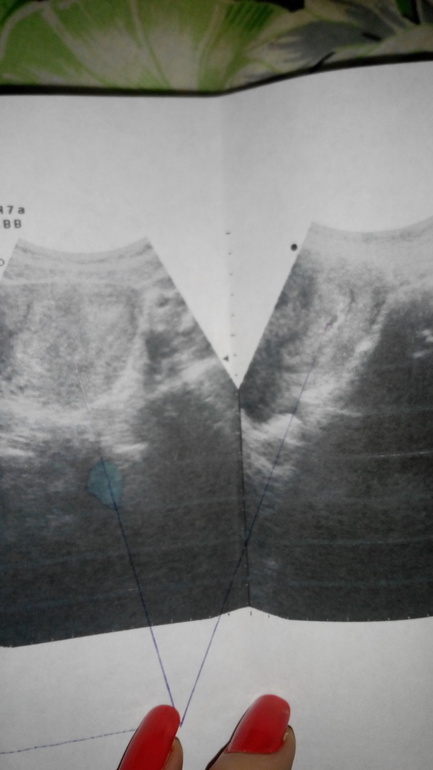

Официально беременная!))

была сегодня на УЗИ все хорошо врач сказал паталогий нет срок 4недели, прийти в 8н. Но есть проблема с мочевиком цистит((